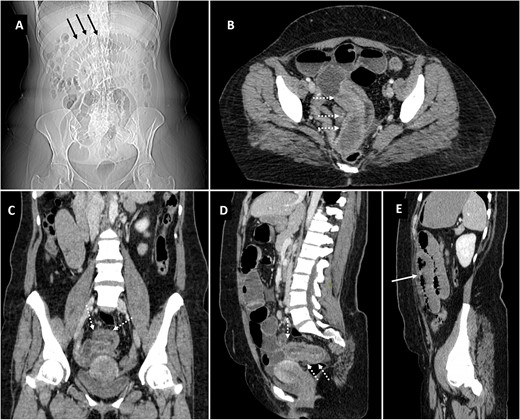

The patient was shifted to the radiology department for screening ultrasonography which revealed dilated small bowel loops with to-and-fro peristalsis with maximum caliber of 3.5 mm. With provisional diagnosis of intestinal obstruction, patient was planned for CT scan to localize the transition point. CT scan (Fig. 1) demonstrated telescoping of one of the pelvic ileal loops into adjacent ileal loop for a length of ~14 cm. The distal bowel segment receiving the prolapsing bowel segment showed circumferential mural thickening measuring approximately 7 mm with resultant dilatation of the proximal jejunal, and mid ileal pelvic loops which showed air fluid levels measuring upto 3.6 cm in maximum caliber. The distal bowel loops beyond this point appeared collapsed. Thus, a diagnosis of ileo-ileal intussuception was established.

Scannogram (A) showing dilated small bowel loops in central abdomen (black arrows). Axial (B), coronal (C) and sagittal (D, E) images of contrast CT showing telescoping of pelvic ileal loop (dotted white arrows) with upstream small bowel obstruction (solid white arrow).